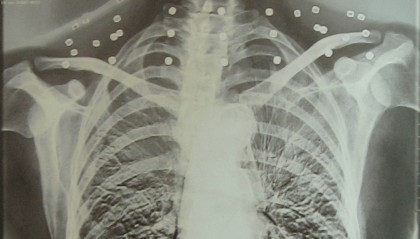

“老先生,您把项链取下来再做CT”

“老先生 您要把项链取下来再做CT” “我从来没戴过项链 你看会不会是弹片?” 这张照片 是今年82...